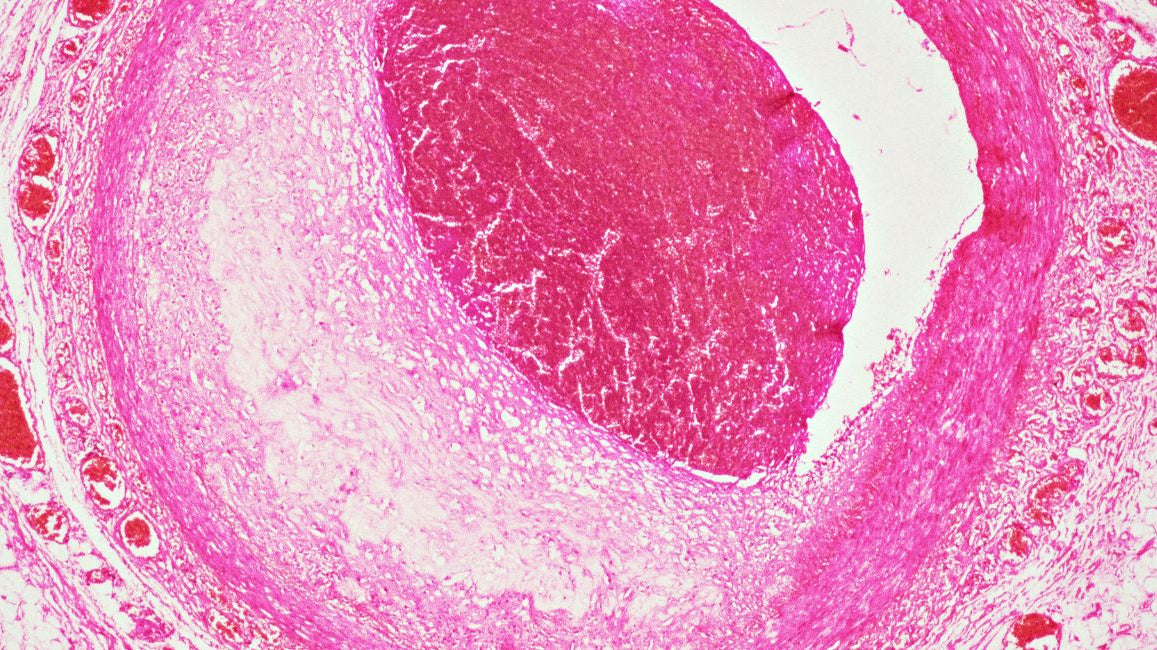

Preventing heartache: sugar intake and your cardiovascular health